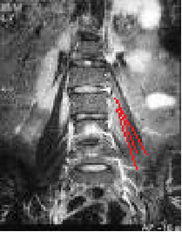

Diskarna:

Disken är den största viktbärande strukturen, om vävnaden belastas ensidigt så kan smärta uppstå utan att det uppstått någon skada i vävnaden

Det gemensamma för uppkomsten av ryggbesvär är en felaktig rörlighet mellan två eller flera kotor. Smärtan kan komma från disken eller från de små kotlederna. Dessa kan i sin tur vara skadade av olika anledningar som; -diskbråck, -kotglidning, -diskdegeneration eller resttillstånd efter en kotfraktur.